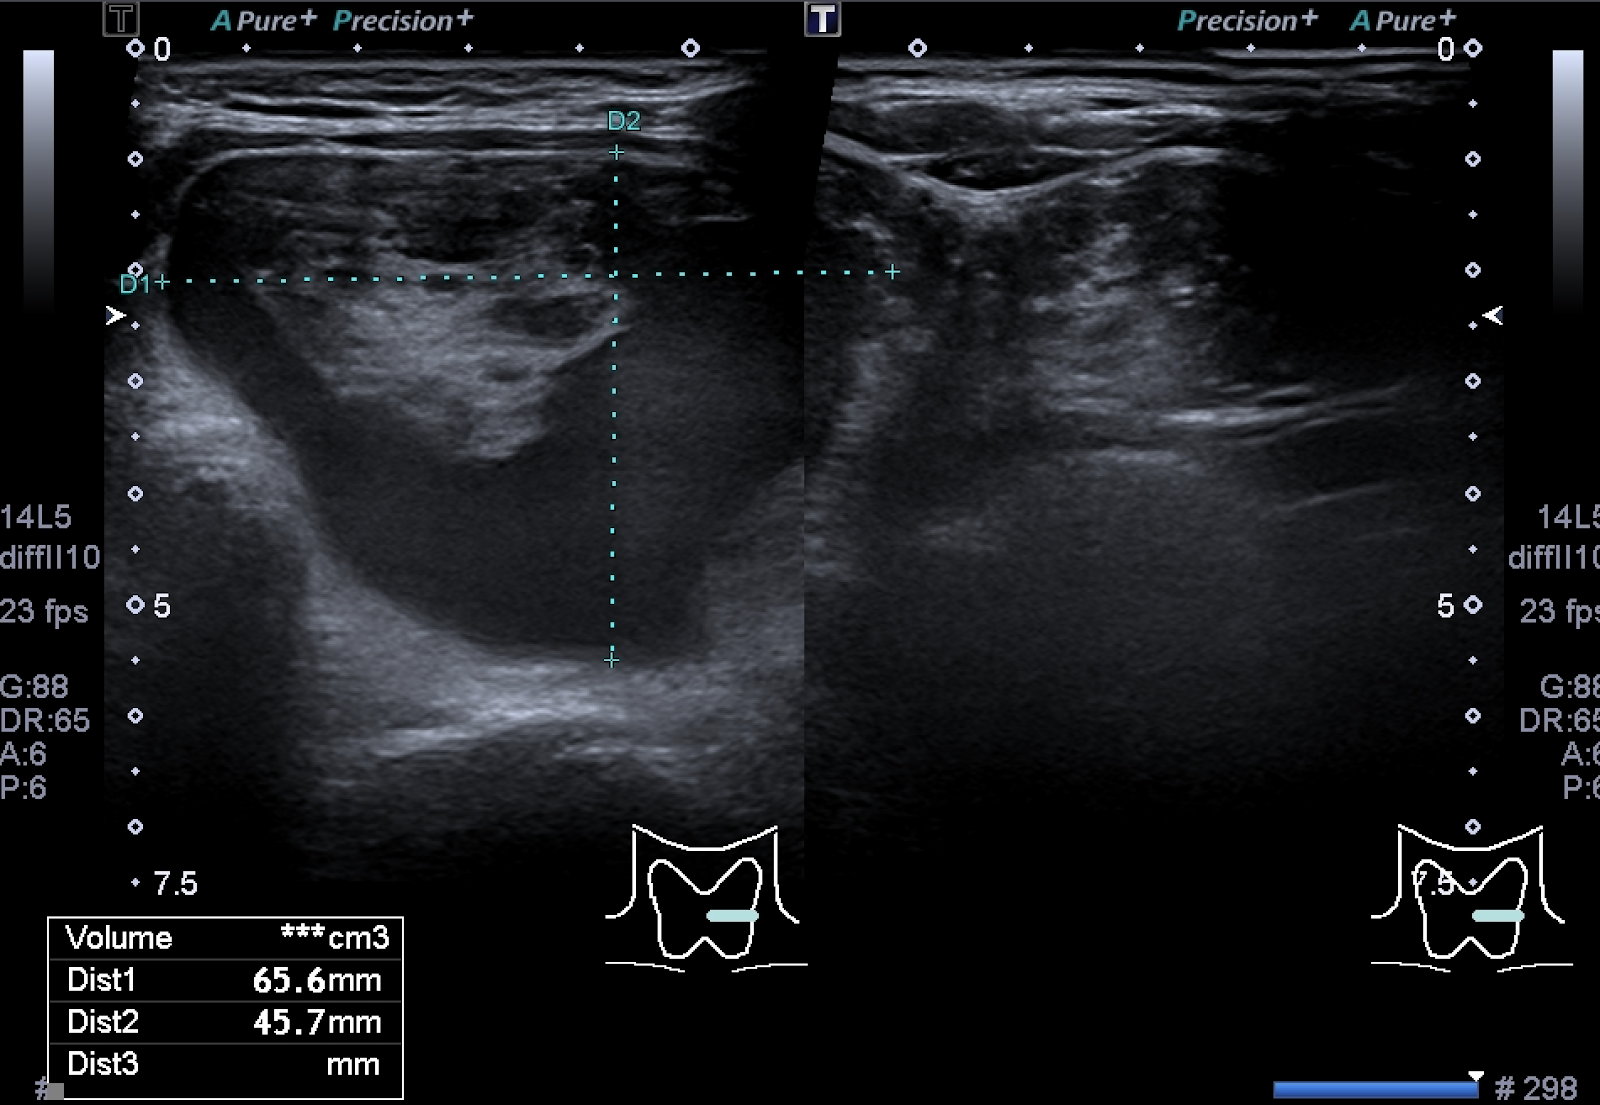

Resultado após alcoolização: volume 1,3mL